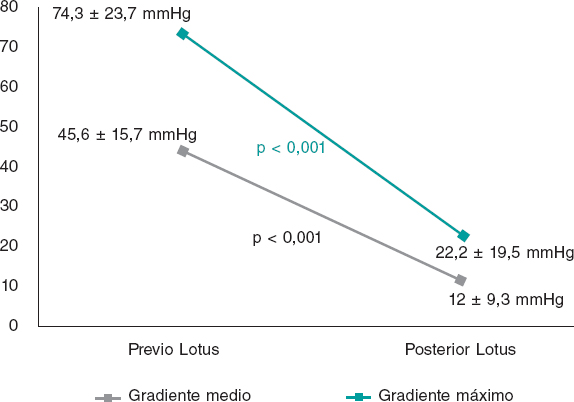

La mayor parte de los pacientes tenían una función sistólica conservada y todos estaban diagnosticados de EAo grave, con un área valvular indexada media de 0,66 ± 0,17 cm2/m2 y unos gradientes aórtico máximo y medio de 74,3 ± 23,7 y 45,6 ± 15,7 mmHg, respectivamente. El 22% de los pacientes presentaba además una IAo al menos de grado moderado (≥ 2).

Tras el implante se observó una reducción significativa de los gradientes transvalvulares, tanto medio como máximo, y del porcentaje de IAo significativa (p < 0,001) (figura 2). En un caso se produjo una fuga periprotésica de grado 2 y no hubo ninguna que fuera más grave. En el caso citado se describe un anillo grande (diámetro medido por tomografía computarizada de 27 mm, valor en los límites superiores de los recomendados por la compañía) y la causa principal de la fuga periprotésica moderada podría ser, por tanto, una escasa sobredimensión de la prótesis con respecto al tamaño del anillo.

Figura 2. Gradientes previos y posteriores al implante.

En cuanto a los parámetros ecocardiográficos, se observó la persistencia de los buenos resultados a largo plazo, sin variaciones significativas en los gradientes valvulares posteriores al TAVI (gradiente medio de 12 ± 9,3 mmHg al alta frente a 12,4 ± 6,8 mmHg a los 3 años; gradiente máximo de 22 ± 19,5 mmHg al alta frente a 24,5 ± 13,2 mmHg a los 3 años). Sin embargo, se detectó trombosis protésica en 2 pacientes (3,5%), diagnosticados ambos en un control ecocardiográfico habitual, sin eventos clínicos asociados. En un caso fue una trombosis precoz, a los 2 meses del implante de la prótesis, en un paciente de 87 años, con disfunción ventricular grave e implante de una Lotus n.º 27, en tratamiento al alta con doble antiagregación. En el otro caso fue una trombosis muy tardía, a los 46 meses tras el implante de la prótesis, en un paciente de 71 años, con disfunción ventricular moderada y Lotus n.º 23. Ambos pacientes mejoraron con tratamiento anticoagulante. En el seguimiento no hubo ningún caso de insuficiencia aórtica periprotésica de grado > 1 y ningún paciente precisó una nueva intervención.